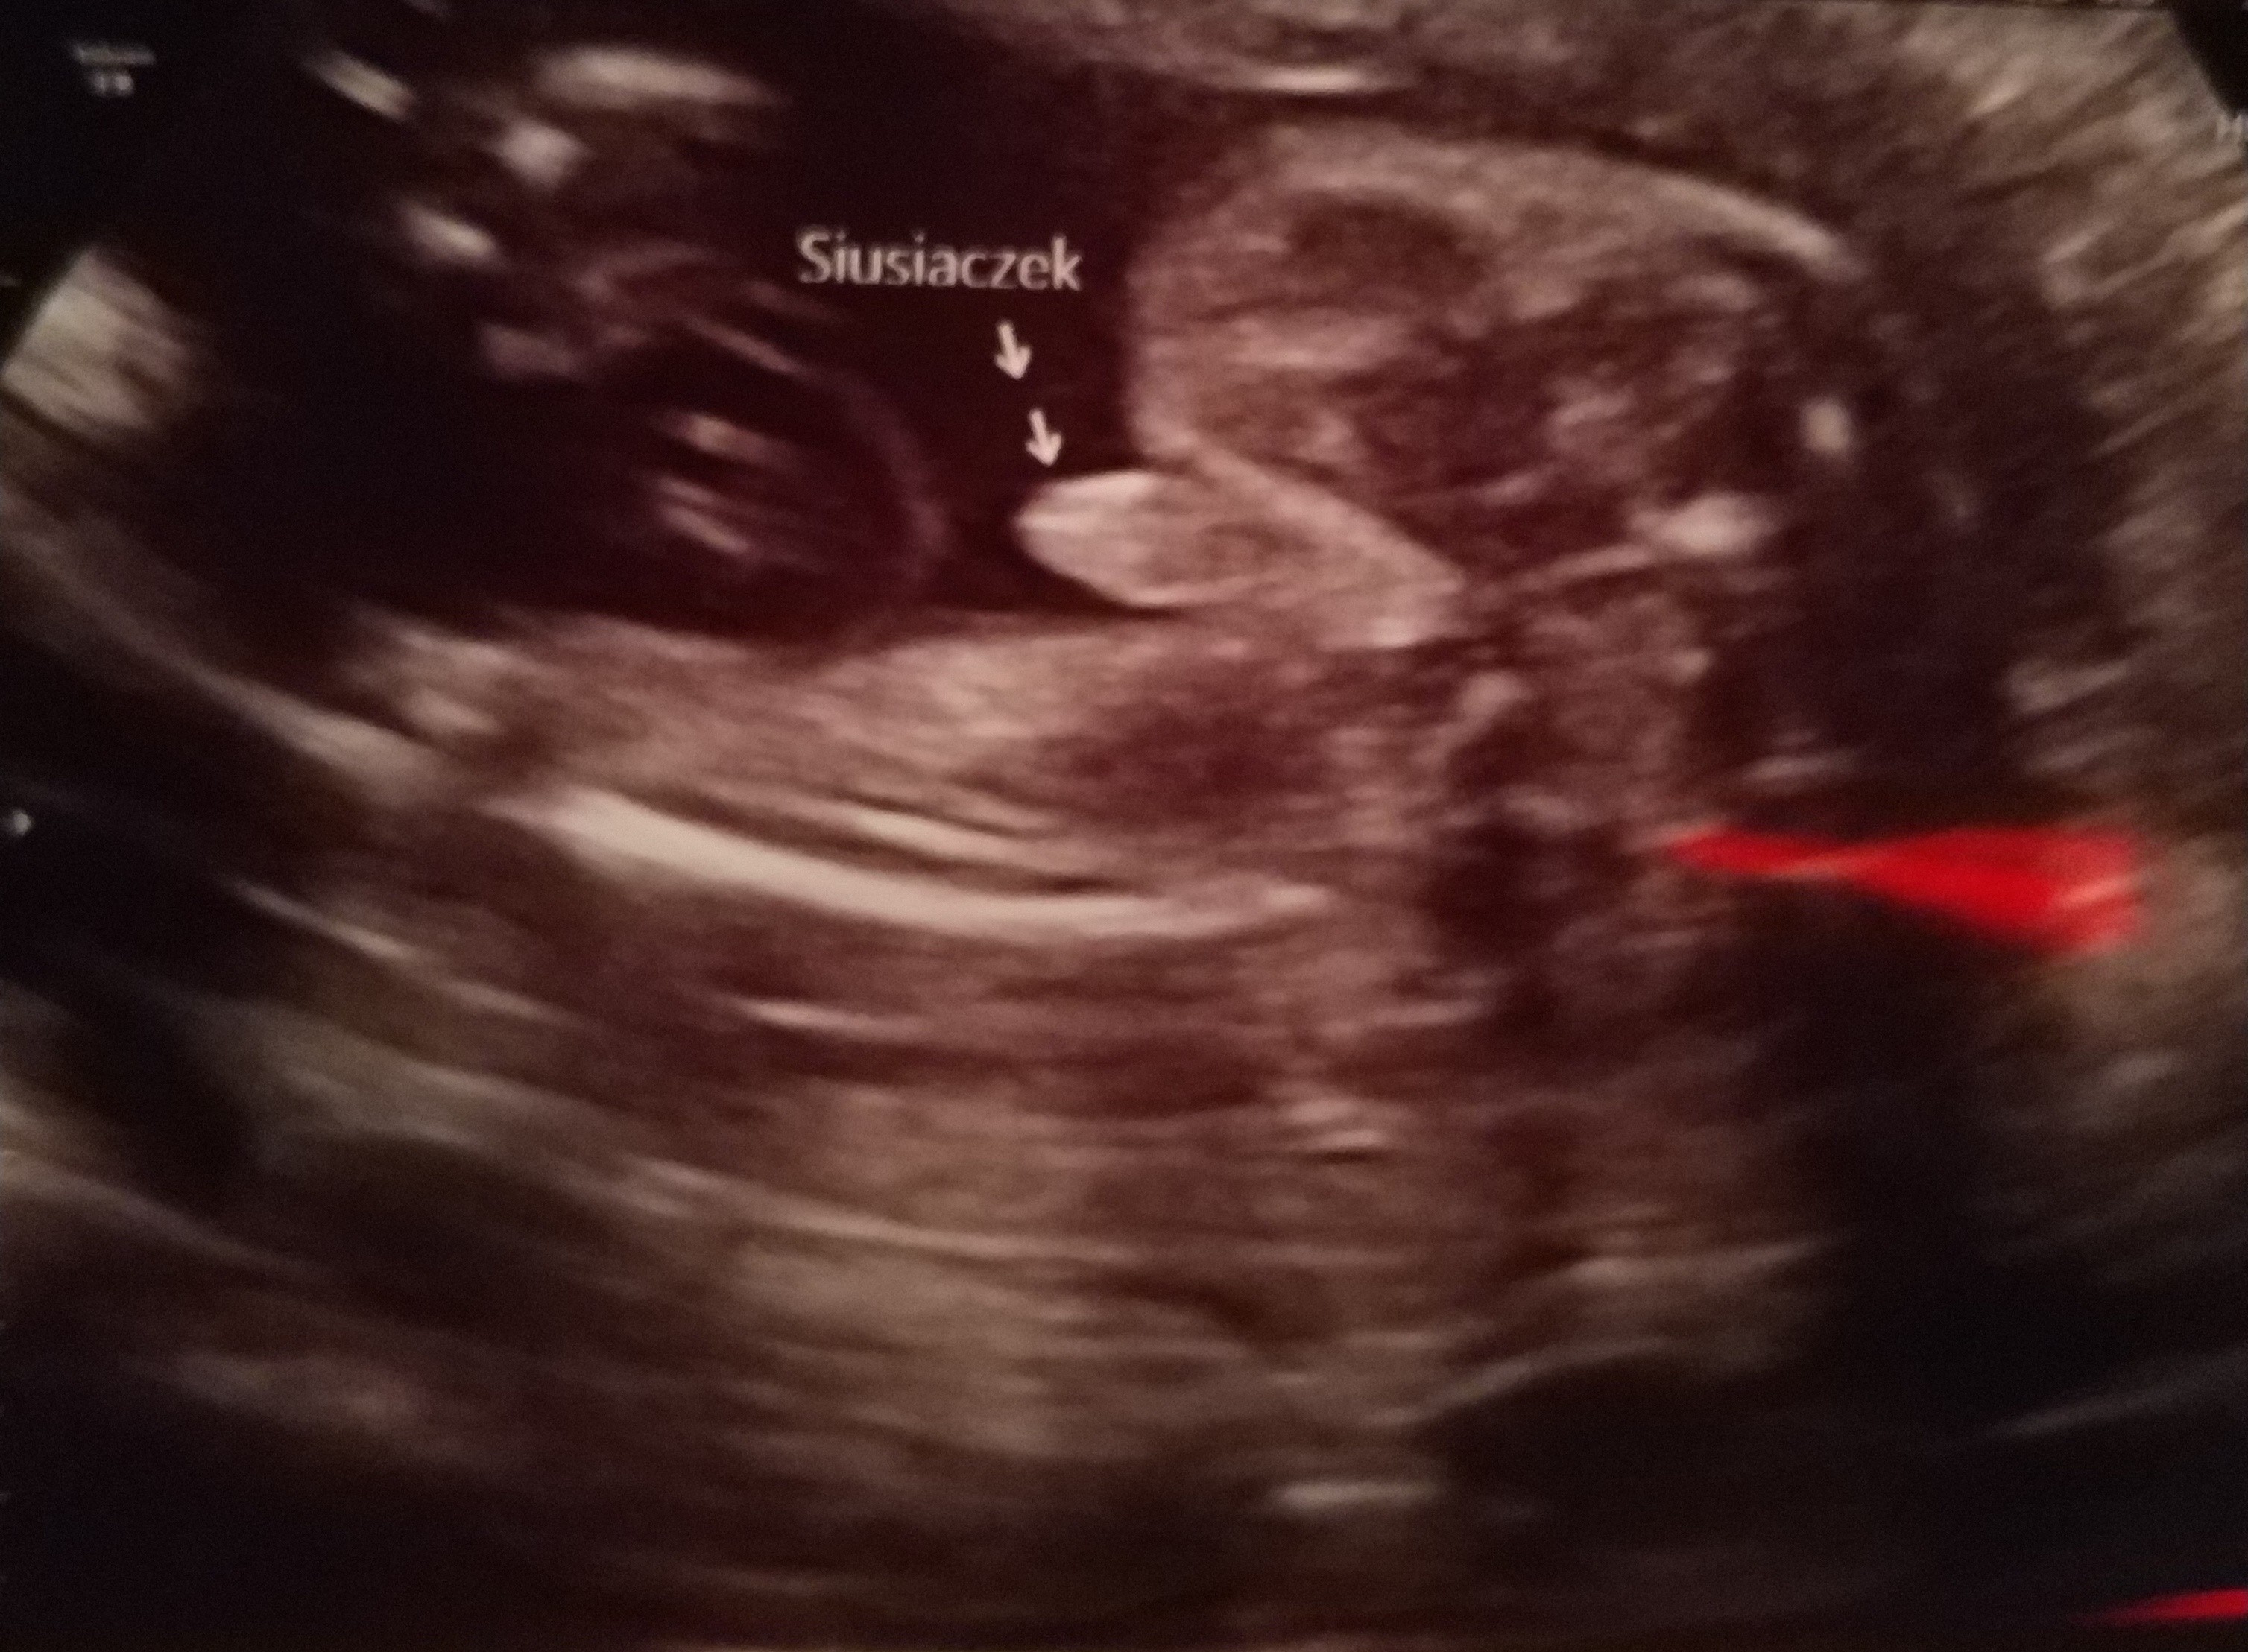

Synus rosnie w siłę i odpowiada 25tc. Ogolnie kazal skontrolowac za 7-9 tyg. wage dziecka bo wyglada na to ze bedzie spory. do tego ulozony na poczatku posladkowo a finalnie poprzecznie. to sie moze z milion razy zmienic ale niezly kombinator z niego. Pan doktor zaznaczyl nam na usg siusiaczka nazywajac go armatką i ze na pewno bedzie straszyl kolezanki w przedszkolu :p

Synus rosnie w siłę i odpowiada 25tc. Ogolnie kazal skontrolowac za 7-9 tyg. wage dziecka bo wyglada na to ze bedzie spory. do tego ulozony na poczatku posladkowo a finalnie poprzecznie. to sie moze z milion razy zmienic ale niezly kombinator z niego. Pan doktor zaznaczyl nam na usg siusiaczka nazywajac go armatką i ze na pewno bedzie straszyl kolezanki w przedszkolu [emoji14]